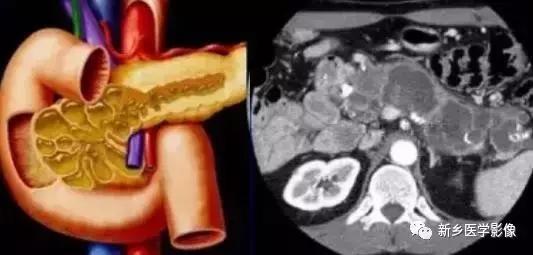

(三)导管内黏液乳头状肿瘤(IPMT):

IPM T 好发于中老年, 50 ~ 70 岁多见, 为低度恶性或有恶性倾向的肿瘤, 有时同一个肿瘤内可见良性、交界性及恶性肿瘤成分。本病预后较好, 由于肿瘤常生长于主胰管, 因而临床上常可表现为反复发作的急性胰腺炎或慢性阻塞性胰腺炎, 65 %左右的患者有腹痛, 45 %的患者有体重减轻, 另外还可表现为恶心呕吐及脂肪泻等。

1.病理:IPM T 起源于主胰管(主胰管型)或主胰管的主要分支(分支型), 发生于主胰管者可累及局部胰管也可弥漫侵及整个主胰管, 发生于胰管分支者后期也常累及主胰管(混合型)。发生于主胰管者主胰管及其主要分支均有非狭窄性扩张,病变区衬以分泌黏液的高柱状上皮, 扩张囊变的胰管内可见黏液栓以及偏平或乳头状生长的壁结节。发生于主胰管大分支的病变大多发生于胰腺钩突,少数发生于胰尾部,早期为多囊状的肿块结构, 与胰腺囊腺瘤颇为相似, 后期病变常累及主胰管, 则与原发于主胰管的病变相似。无论是发生于主胰管还是其主要分支的病变, 其病变均与主胰管相通, 这与胰腺囊腺瘤明显不同。由于乳头状新生物或黏液栓阻塞胰管, 常继发胰腺炎症。

2.影像学诊断:主胰管型的病变C T 、M RI 上可表现为主胰管囊状扩张,其主要分支也可见扩张,胰腺萎缩, 有时与慢性阻塞性胰腺炎难以鉴别, 如果显示了扩张胰管内的壁结节或黏液栓对诊断颇有帮助, 薄层扫描及变换体位对显示壁结节和黏液栓有好处, 黏液栓随重力总位于囊腔下壁。位于胰头部的病变还可引起扩张的壶腹突向十二指肠腔。发生于胰管分支的病变表现为多房状囊性肿块, 常位于胰头钩突, 内可见间隔, 表现与囊腺瘤相似, 后期病变累及主胰管则出现主胰管的扩张及其腔内的壁结节和黏液栓。MRCP 及ERCP 对本病的诊断非常有帮助, 特别是ERCP , 内镜下即可见乳头溢出黏液样物,有时可见突向十二指肠的扩张乳头, 注射造影剂后容易显示壁结节和黏液栓造成的充盈缺损, 病变与主胰管相通有助于鉴别诊断。